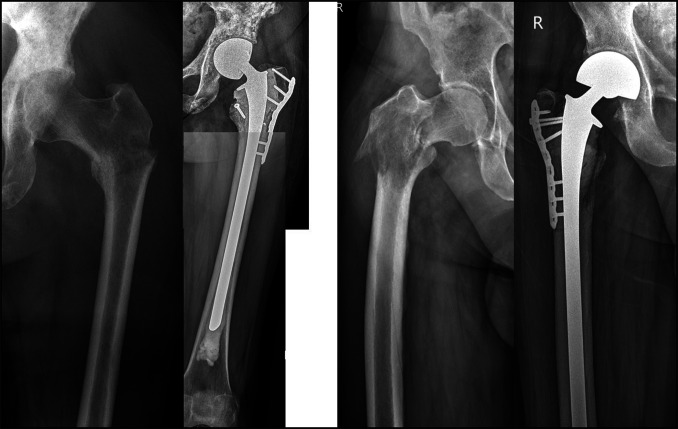

Background: The incidence of metastatic cancer continues to increase, becoming a prevalent condition in oncology orthopaedic practice. The proximal femur is the third most common site of skeletal metastases. Two possible options for endoprosthetic reconstruction of proximal femur metastasis include proximal femur resection and replacement with megaprosthesis and hemiarthroplasty with a long-cemented revision stem.

Methods: To facilitate better decision making, we conducted a retrospective study comparing these alternatives. This is a single-institution, retrospective, observational study. Patients with metastatic disease of proximal femur who had a reconstruction with either a proximal femoral replacement (group A, 27 patients) or reconstruction using a hemiarthroplasty with long revision cemented stem (group B, 31 patients) were included for analysis.

Abstract Image